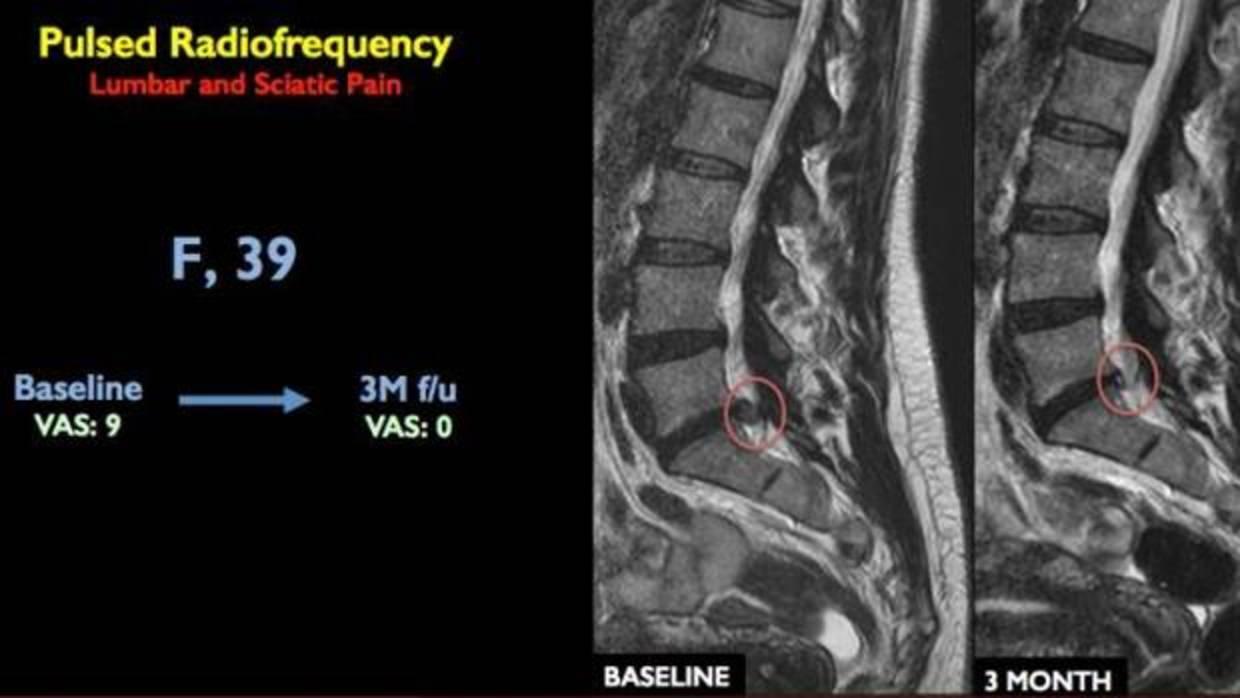

La nueva terapia guiada por imagen y mínimamente invasiva permite que el 90% de los pacientes con hernia discal no tengan que pasar por el quirófano

El alivio del dolor se mantiene a los tres meses del tratamiento SAPIENZA UNIVERSITÀ DI ROMA

El estudio fue llevado a cabo con la participación de 80 pacientes con dolor lumbar por una hernia de disco y al menos tres meses de duración que, sin haber pasado quirófano, no respondían a los tratamientos conservadores convencionales –incluido el ejercicio y la medicación–. Así, y en aras de curar su dolencia, los autores los sometieron a un procedimiento radiológico mínimamente invasivo en el que, con ayuda de un escáner –tomografía axial computarizada (TAC)–, se guiaba una aguja hasta el área de la hernia discal y la raíz nerviosa, se introducía una sonda a través de la punta de la aguja y se administraba energía de radiofrecuencia pulsada sobre el área durante un periodo de 10 minutos. Una intervención en la que ni la aguja ni la sonda tocaban el disco intervertebral pero que, de acuerdo con los resultados, es ciertamente eficaz.

Concretamente, el 81% de los participantes estuvieron libres de dolor durante un año con una única sesión de 10 minutos. Un beneficio que alcanzaron otros seis pacientes tras someterse a una segunda sesión. Y gracias a la intervención, el 90% de los pacientes evitaron tener que pasar por el quirófano .